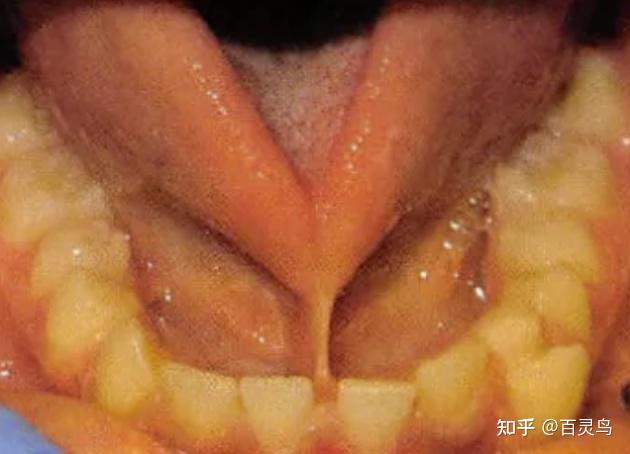

舌系带过短,连到舌尖,舔不到上牙齿背.

不能伸到口外;在舌体前伸或牵拉时可见到舌背出现小凹陷,舌尖呈"w"型

舌系带过短的孩子一般发音不清集中在舌尖后音(zh,ch,sh,r),舌尖中音